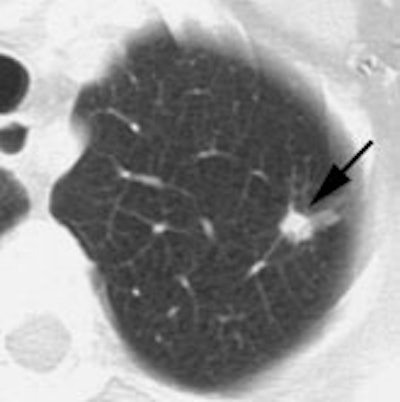

Example: The CT scan in this patient demonstrated a small nodule in the left upper lobe (black arrow). PET-FDG images demonstrate very intense accumulation of the tracer within the lesion (white arrow), which was a non-small cell lung cancer. (Case courtesy of H. Page McAdams MD, Department of Radiology, Duke University Medical Center)